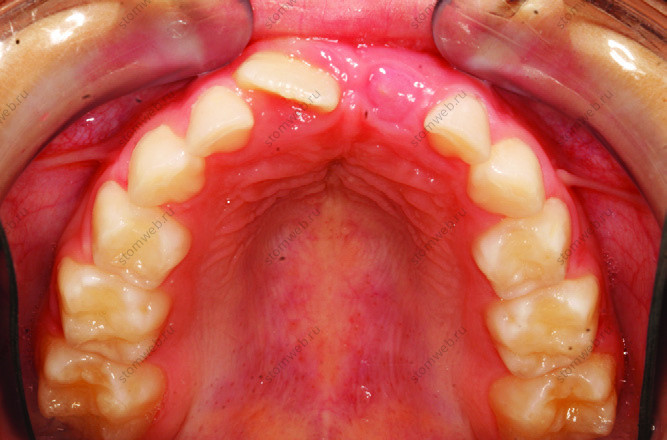

Рисунок 1. A. Зауженная верхняя челюсть, нет места для боковых резцов.

Рисунок 1. B. Травматическая окклюзия верхнего левого центрального резца.

Рисунок 1. C. Зауженная верхняя челюсть, нет места для верхних центральных и боковых резцов.

Рисунок 1. D. Зауженная нижняя челюсть, нет места для нижних центральных и боковых резцов.

Рисунок 1. I. Зауженная арка верхней челюсти, дефицит места для верхних центральных и боковых резцов.

Рисунок 1. M. Зауженная арка улыбки, дефицит места для верхних и нижних центральных и боковых резцов.